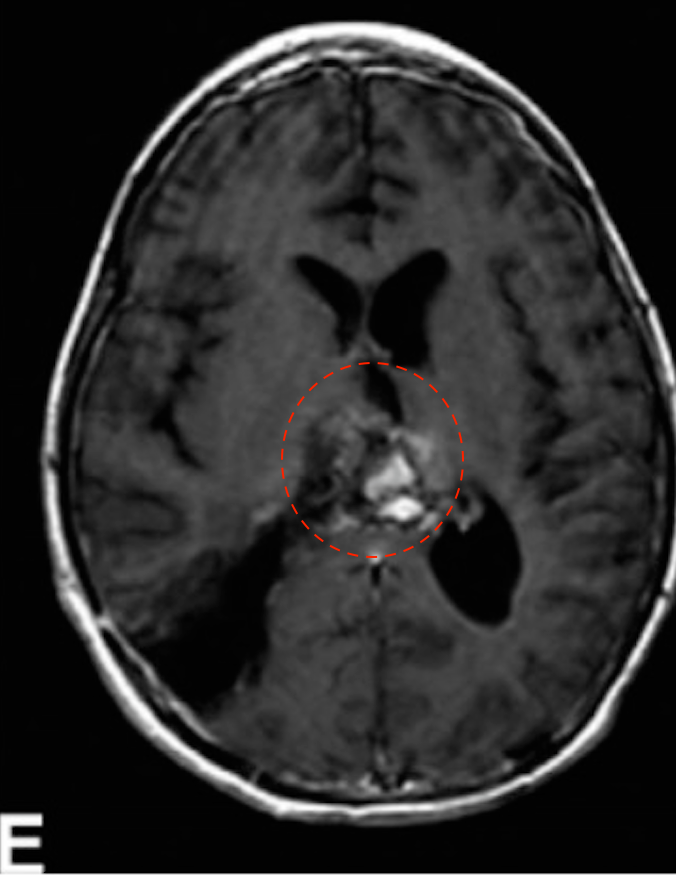

(E)第二次手术,经右顶叶经皮质入路行次全切除术,术后T1增强MRI为WHO 2级室管膜瘤,病人进行局部放疗。